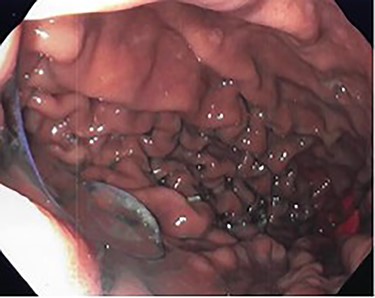

She underwent an upper gastrointestinal series that showed a normal-appearing stomach without any evidence of her prior gastroplasty, moderately sized hiatal hernia and slight delay in passage of contrast through the gastroesophageal junction (Fig. 1). On subsequent endoscopy, she was noted to have multiple loosely placed sutures within the gastric lumen along the greater curvature (Fig. 2), as well as a large-sized paraesophageal hernia.

Intraoperative endoscopy showing loose gastroplasty sutures along the greater curvature of the stomach.

Preoperative endoscopy (post gastroplasty) showing the body of the stomach without restrictive sleeve appearance.

Patient subsequently underwent a robotically assisted laparoscopic paraesophageal hernia repair with mesh, partial gastrectomy with removal of gastric foreign bodies, and flexible endoscopy. Intraoperatively via initial laparoscopic approach, there was only noted to be small dimples along the greater gastric curve without any noticeable plication (Fig. 3). The stomach was twisted up into the hiatal hernia. Multiple permanent sutures with T-fasteners were seen on endoscopy, and attempts were made to remove these endoscopically without success. These sutures were not of full thickness, so a gastrotomy was made to remove them. Partial gastrectomy was performed, including the fundus. The diaphragm was repaired with interrupted silk sutures and reinforced with a bioabsorbable mesh. The patient recovered well and was discharged home on postoperative day two tolerating a diet. She was seen at follow-up with complete resolution of her preoperative symptoms.